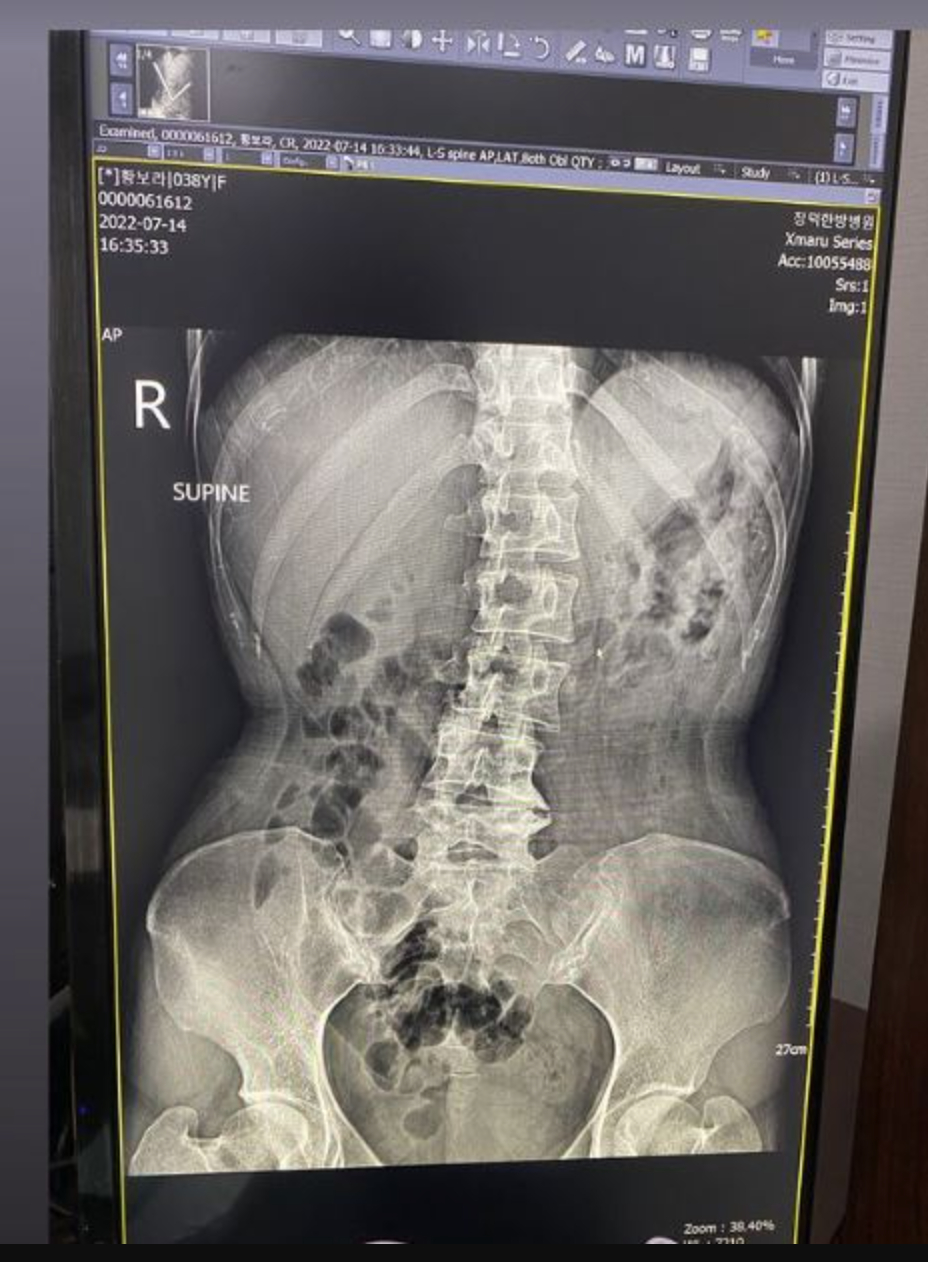

황보라는 15일 자신의 인스타그램 스토리를 통해 병원에서 찍은 것으로 보이는 자신의 허리 부분을 찍은 사진을 공개했다.

황보라는 사진과 함께 "심각한 내 허리 거기가 창피하게 가스까지 ㅜㅜ 50-60대라는데 허리가. 이제 무조건 근력 운동해야겠어요. 골프는 잠정 은퇴합니다"라고 적었다.